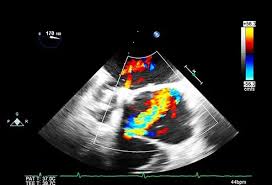

Echocardiograms